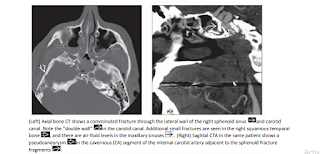

Head & Neck Emergency:Diagnostic Imaging (Click on image to magnify). Get link Facebook X Pinterest Email Other Apps - February 08, 2020 Get link Facebook X Pinterest Email Other Apps Comments